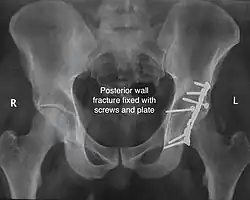

Posterior wall fracture fixed with screws and plate -

| Posterior wall | This is the most common variety of acetabular fracture. It typically occurs due to dashboard injury; when a person travelling in a vehicle involved in a head-on collision, the force applied over the flexed knee travels along the femur bone to the head of the femur, breaking the posterior wall of the acetabulum. The head of the femur is dislocated outside the joint. | T shape | When a transverse fracture also had a vertical fracture line, it is called a T shape fracture. Here the innominate bone is broken in such a way that all three parts of it, the ilium, the ischium and the pubis are separated from one another. This is a three part fracture. Though both columns are broken, the weight bearing dome is still attached to the main part of the ilium and hence it is not a true fracture of both columns.

| Posterior column | As with posterior wall injury, this also typically occurs due to dash board injury. | Posterior column + Posterior wall | These fractures are extensions of elementary fractures. With the involvement of the posterior wall, the difficulty in treatment increases. These fractures are rarely amenable to non-surgical treatment. Due to posterior wall fracture, the hip is usually dislocated posteriorly, requiring immediate reduction of dislocation and surgical reconstruction after a few days.

The final management depends on the size of the fragment(s), stability and congruence of the joint. In some cases traction for six to eight weeks may be the only treatment required; however, surgical fixation using screw(s) and plate(s) may be required if the injury is more complex. The latter treatment will be called for if bone fragments do not fall into place, or if they are found in the joint, or if the joint itself is unstable.